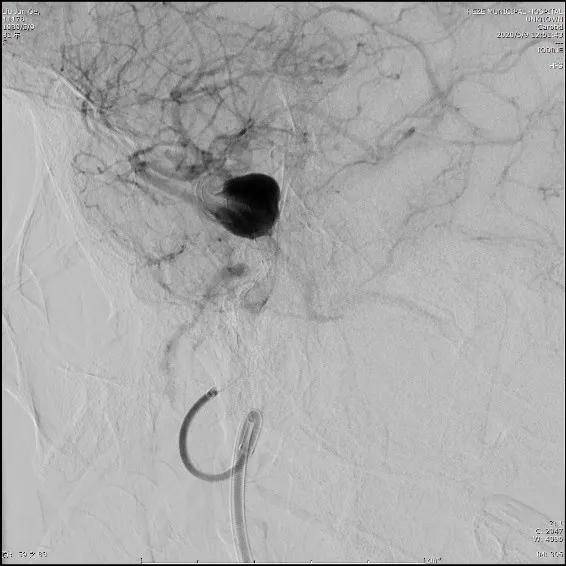

选择5.0×45mm Tubridge®支架,成功释放,覆盖动脉瘤,造影见动脉瘤腔内造影剂明显滞留。

结束手术,患者麻醉清醒后安全返回病房,无神经功能缺失。5天后,患者康复出院。